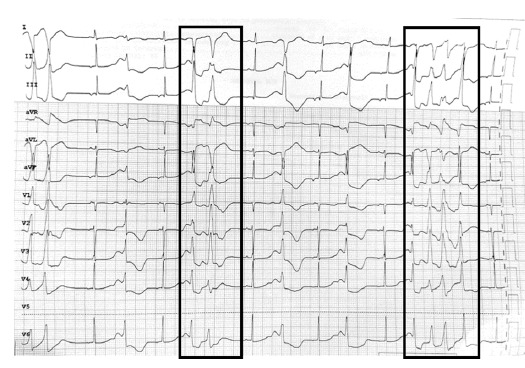

Case presentation: We report the case of a young female patient who presented with multiple episodes of tonic posturing and altered level of consciousness. Diagnostic evaluation revealed severe hypocalcemia with hypomagnesemia, QT prolongation, and episodes of non-sustained ventricular tachycardia. The condition was managed with calcium and magnesium supplementation. Further investigations revealed a novel missense mutation in transient receptor potential melastatin 3 (TRPM3).

Discussion: Hypocalcemic seizures are rare in adults and are typically associated with severe hypocalcemia and cardiovascular instability, including ventricular dysrhythmias. The differential diagnoses in this case included primary hypoparathyroidism, Bartter syndrome type 5 (CaSR (calcium-sensing receptor) mutation), Gitelman syndrome, and claudin mutations. TRPM3 is highly expressed in kidney tissue, playing a role in the resorption of calcium and divalent ions. However, further research is needed to confirm its role in calcium homeostasis.